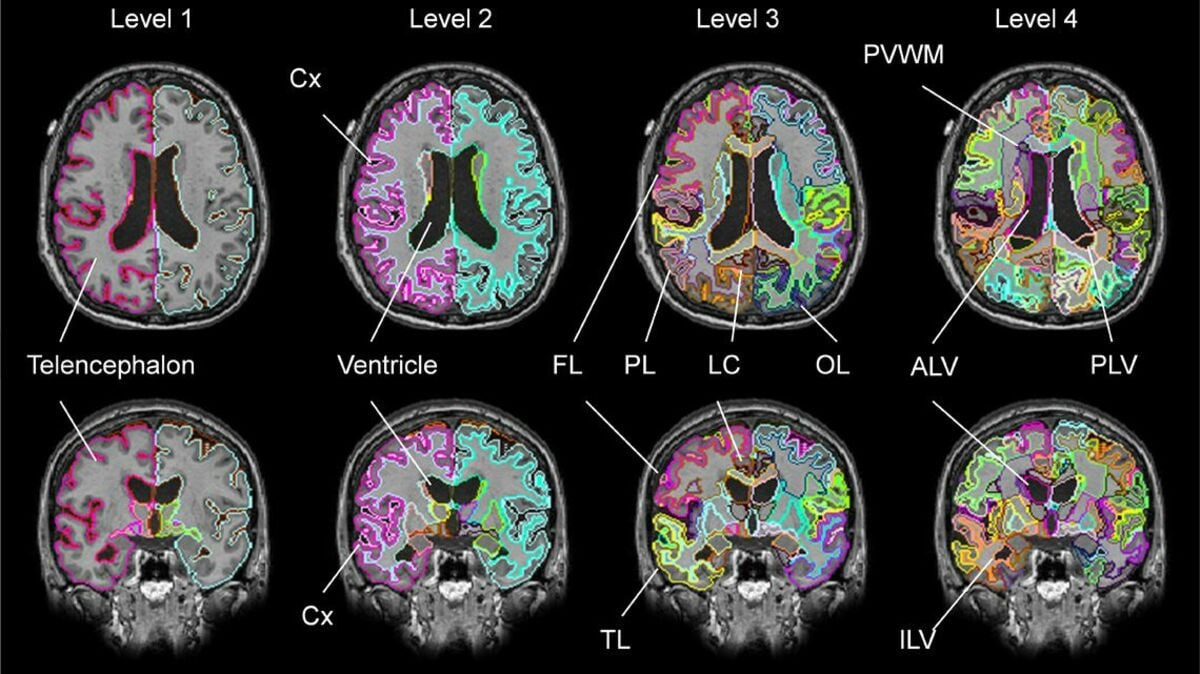

뇌 MRI는 강한 자기장과 고주파를 이용해 뇌 조직을 자세히 촬영하는 검사입니다. CT와 비교하면 뇌의 연부조직, 신경계 구조, 작은 병변을 더 세밀하게 보는 데 강점이 있어서 뇌종양, 뇌경색, 염증, 탈수초성 질환, 뇌출혈 후 변화, 원인 미상의 신경학적 증상 평가 등에 널리 사용됩니다.